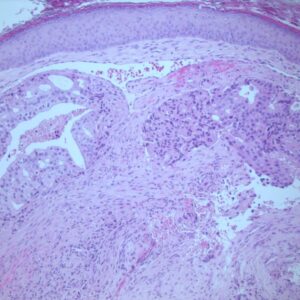

38-year-old female underwent right nephrectomy for a tumour mass